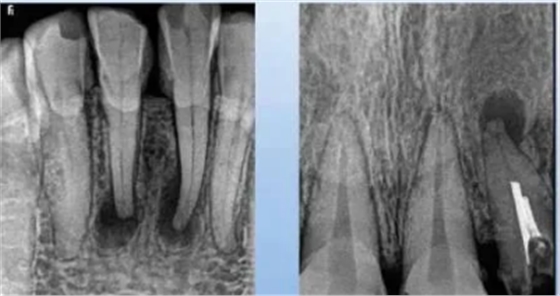

1、急性浆液性根尖周炎

病理及临床:牙周膜充血,牙骨质和牙槽骨无明显改变。患牙伸长,叩痛明显。

X线表现:根尖区牙周膜间隙略有增宽。

2.急性化脓性根尖周炎

病理及临床:牙周膜渗出物增多,白细胞坏死溶解形成脓液。症状明显,有自发性、持续性搏动性疼痛,叩痛明显。

X线表现:根尖部不规则,小区域的透射影,边界不整齐,范围局限。

二、慢性根尖周炎

1.慢性根尖脓肿

病理及临床:根尖部脓液被纤维组织包围,或由根尖肉芽肿得中央细胞坏死、液化形成。多无自觉症状,时有龈瘘。

X线表现:根尖区边界不清楚但不锐利的透射区,密度不规则。

2.根尖肉芽肿

病理及临床:致密的结缔组织包绕根尖的肉芽组织。常无症状,咬合无力,牙伸长感。

X线表现:范围较小,周界清晰,无致密骨壁线。